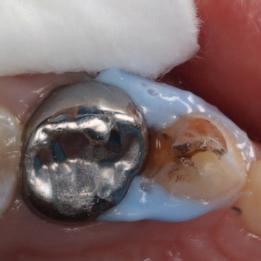

Create a flipbook

Issuu converts static files into: digital portfolios, online yearbooks, online catalogs, digital photo albums and more. Sign up and create your flipbook.